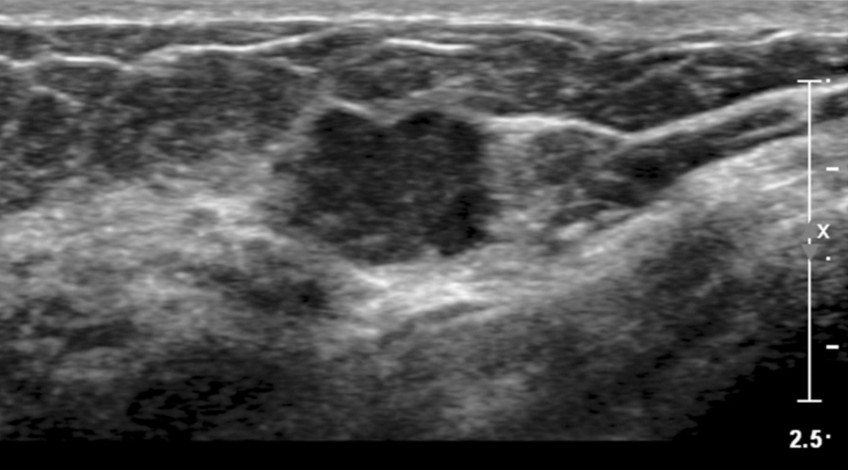

Ecotomografía Mamaria

- ¿Qué es? Examen que ser realiza para estudiar el tejido mamario, frecuentemente en forma complementaria a la Mamografía. Por lo general se realizan ambos exámenes en la misma cita, pero siempre la Mamografía en primer lugar. En caso de que el paciente tenga una mamografía anterior, debe llevar la última realizada, de no más de 6 meses de antigüedad.